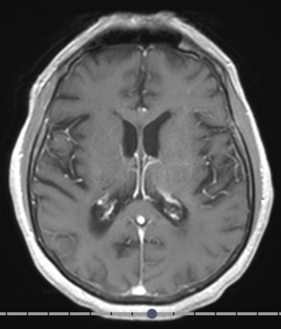

Standardized body region labelling of individual images provides data that can improve human and computer use of medical images. A CNN-based classifier was developed to identify body regions in CT and MRI. 17 CT (18 MRI) body regions covering the entire human body were defined for the classification task. Three retrospective databases were built for the AI model training, validation, and testing, with a balanced distribution of studies per body region. The test databases originated from a different healthcare network. Accuracy, recall and precision of the classifier was evaluated for patient age, patient gender, institution, scanner manufacturer, contrast, slice thickness, MRI sequence, and CT kernel. The data included a retrospective cohort of 2,934 anonymized CT cases (training: 1,804 studies, validation: 602 studies, test: 528 studies) and 3,185 anonymized MRI cases (training: 1,911 studies, validation: 636 studies, test: 638 studies). 27 institutions from primary care hospitals, community hospitals and imaging centers contributed to the test datasets. The data included cases of all genders in equal proportions and subjects aged from a few months old to +90 years old. An image-level prediction accuracy of 91.9% (90.2 - 92.1) for CT, and 94.2% (92.0 - 95.6) for MRI was achieved. The classification results were robust across all body regions and confounding factors. Due to limited data, performance results for subjects under 10 years-old could not be reliably evaluated. We show that deep learning models can classify CT and MRI images by body region including lower and upper extremities with high accuracy.